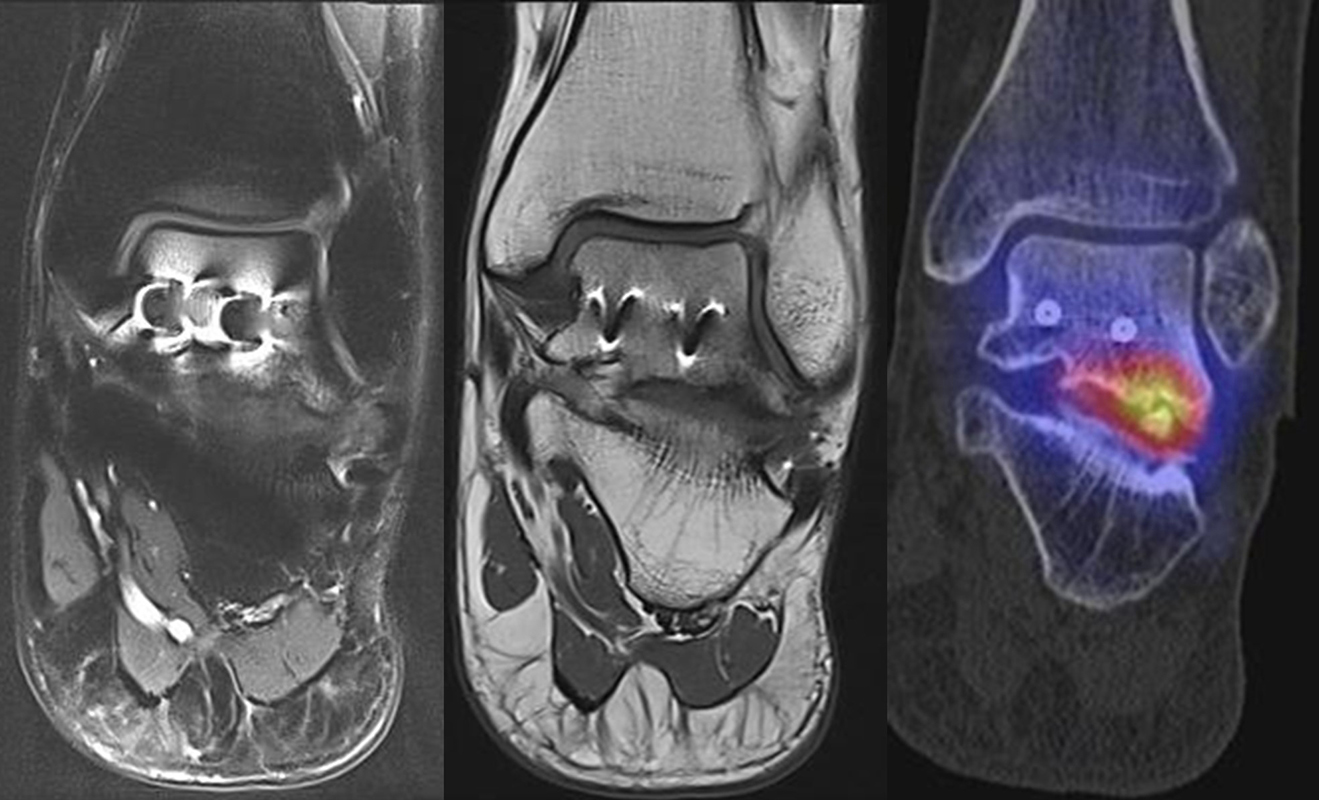

Abbildung 2.1.

Bildbeispiele symptomatische OCL

Zum Lesen der Bildbeschreibung und zur Vollansicht bitte das Bild anklicken. Bild: H. C. Rischke

Abbildung 2.2.

Bilder eines Patienten mit Z. n. mehrfachen Sprunggelenksdistorsionen in der Vergangenheit, besonders heftige Distorsion des linken Sprunggelenkes 5 Wochen vor der Untersuchung. Die SPECT/CT zeigt eine instabile osteochondrale Läsion mit deutlicher Aktivierung.

Abbildung 2.3.

Klärung bei Schmerzen im rechten OSG bei OCL an der medialen Talusschulter. Z. n. OSG-Distorsion vor 2 Jahren und Z. n. OSG-Fraktur / Syndesomosenruptur. Ausgedehnte OCL, hier jedoch kein erhöhter Knochenmetabolismus; lediglich Nachweis einer Stressreaktion im Bereich der Synchondrose eines Os trigonum als Schmerzursache.